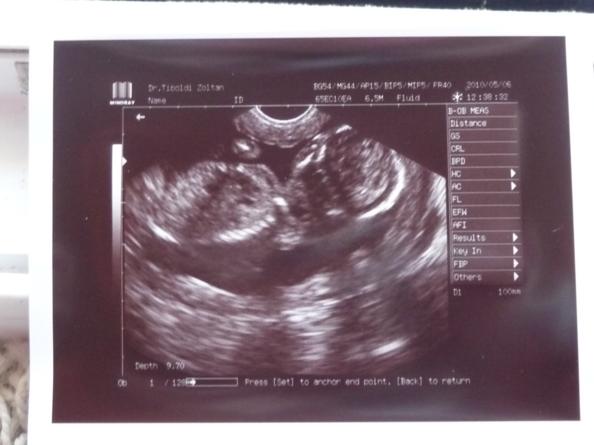

A tegnapi termés:)